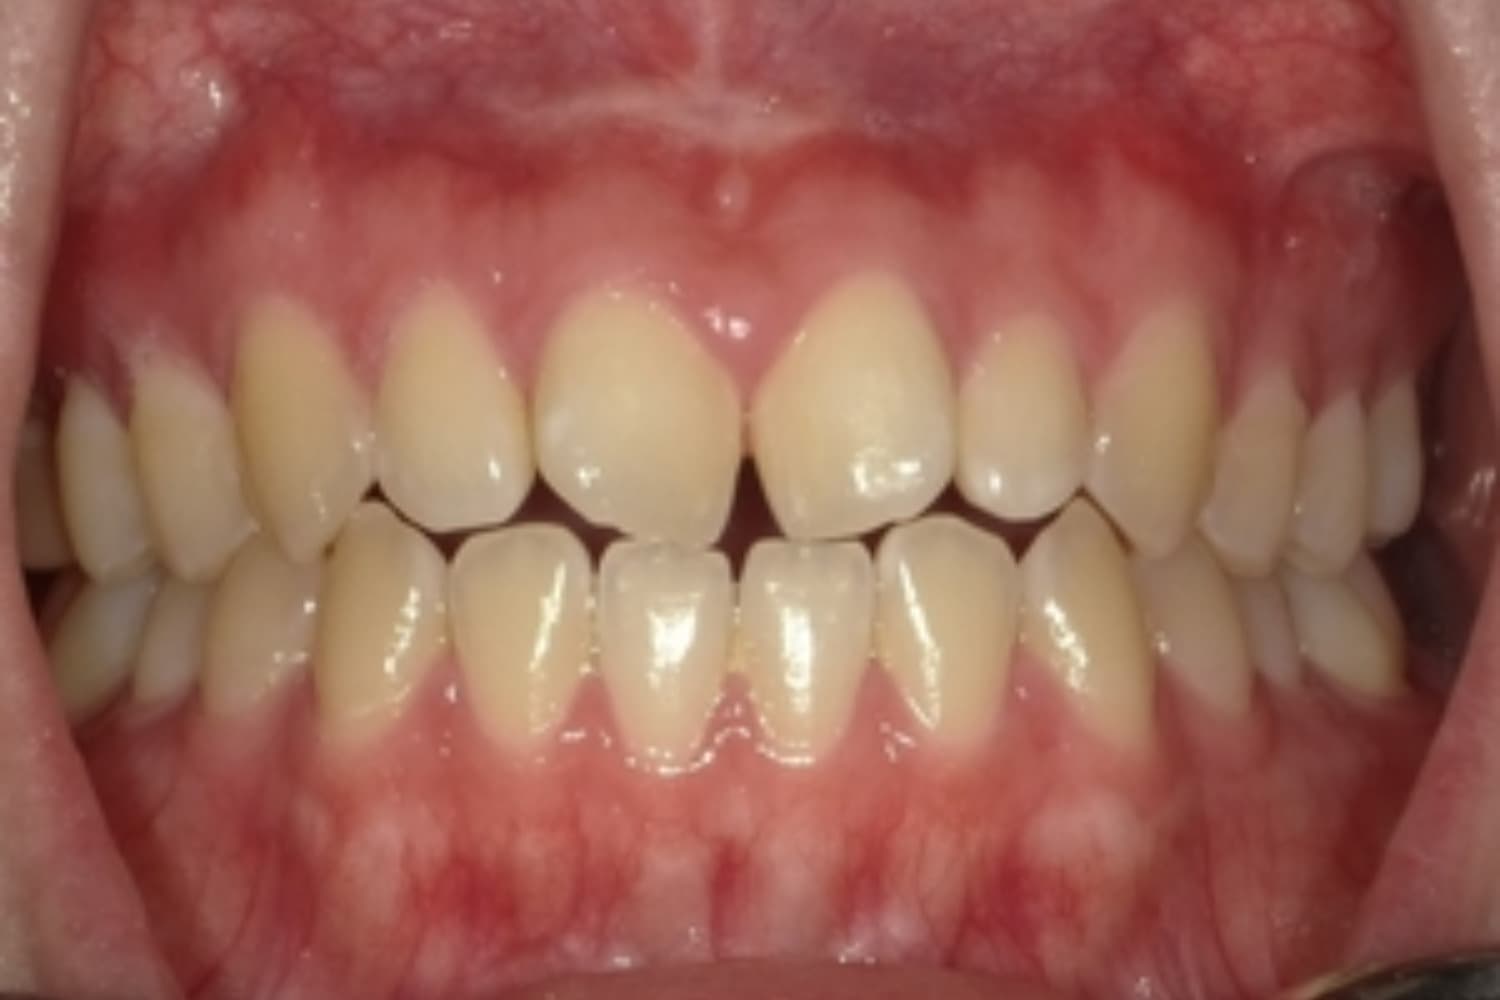

すきっぱ(空隙歯列)

Before

After

気になる前歯の隙間と前歯のガタガタをマウスピース矯正(インビザライン)にて治療

治療期間

1年5カ月

費用

66万円(税込)